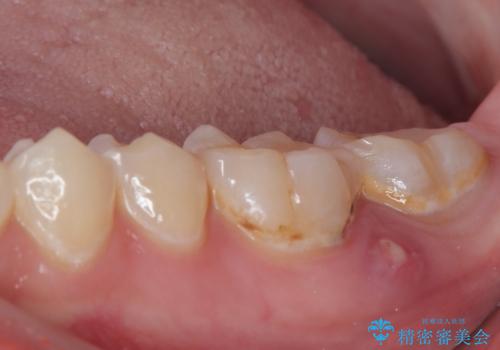

- 食事などで噛んだときに奥歯に痛みを感じるとのことで来院された患者様です。

奥に埋もれている親知らずが原因でむし歯になり、以前に根管治療を行った歯が痛みの原因であり、再度根管治療が必要な状態でした。

根管治療を行った歯は原則としてクラウンによる補綴治療が必要となるため、事前に親知らずを抜歯し、その後根管治療を行うこととしました。